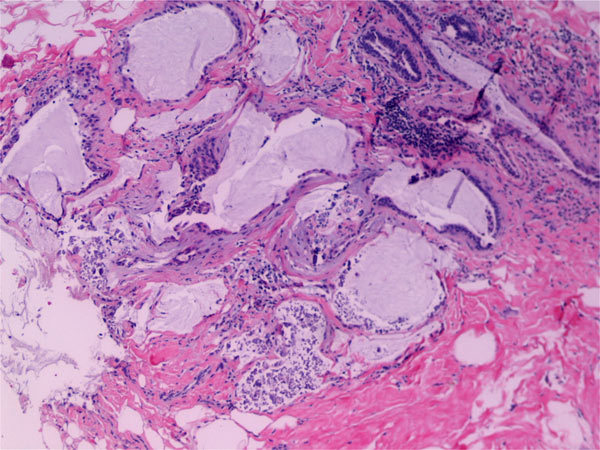

Microglandular adenosis

DDx?

Histology?

Tubular adenoma

DDx

Tubular carcinoma

Adenomyoepithelioma